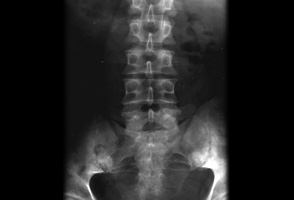

Radiografia simples mostrando sacroileíte bilateral em um paciente com espondilite anquilosante

BMJ 2006;333;581-585. © BMJ Publishing Group Ltd 2009